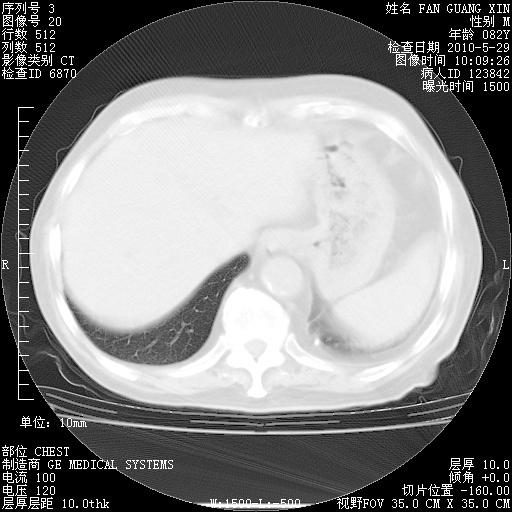

再治疗10天后的肺部CT

再治疗10天后的肺部CT 纵膈窗

阅读此次胸部CT,肺间质渗出性改变较入院时有吸收。目前从体温、白细胞、中性分叶明显增高,肯定存在细菌感染(发生医院感染哦,若无消化道及泌尿系统等感染的依据,肺部感染可能大)。若你院头孢哌酮舒巴坦钠耐药率较高,同意你的方案,若48小时体温仍高,可考虑使用碳青霉稀类抗菌药物,同时可予超声雾化、注意滴数时加大液体量。白蛋白33.30g/L较低哦,需加强营养等支持治疗。